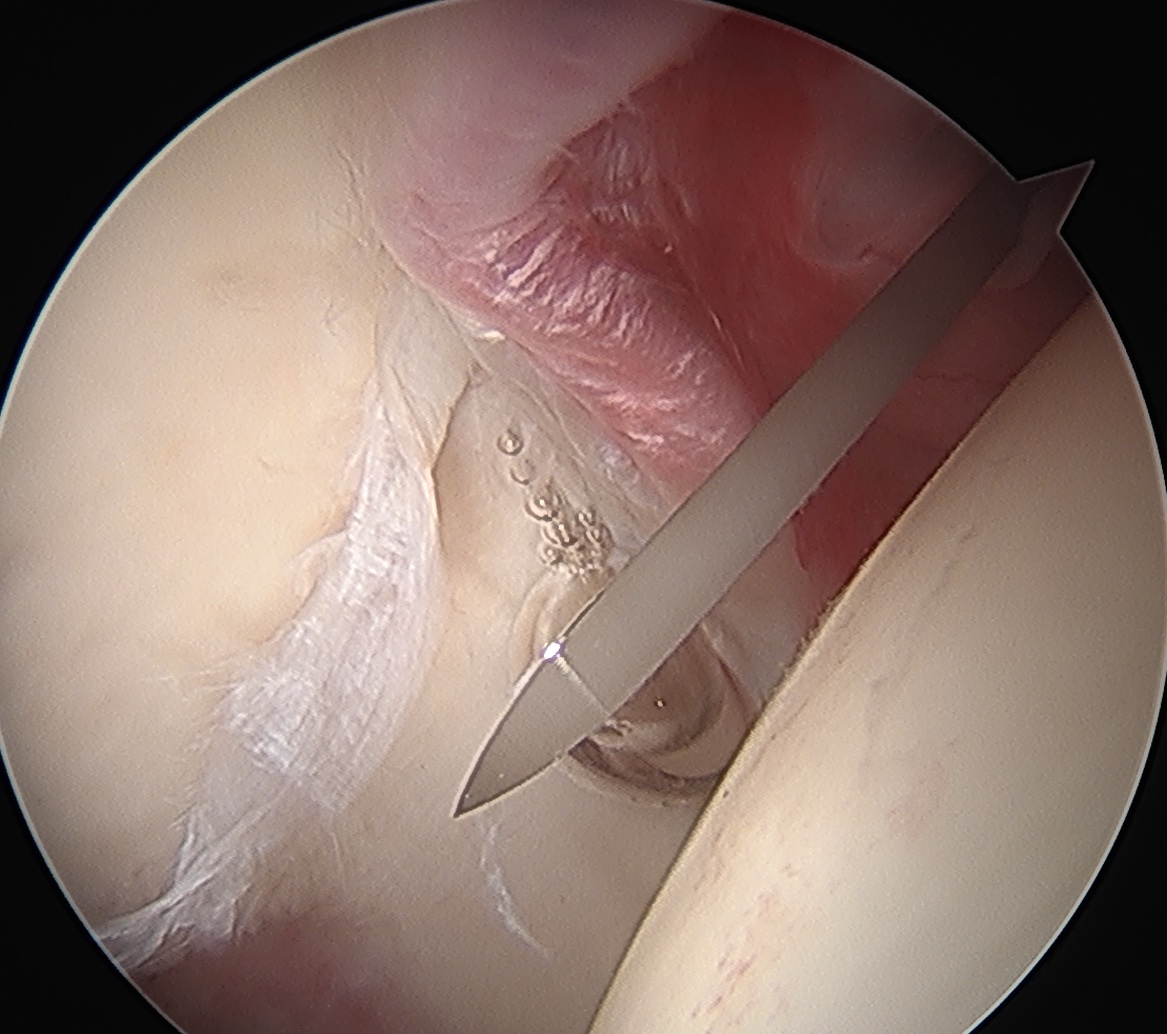

Mid Anterior portal

- stay lateral to line drawn down from ASIS to prevent NV injury

- aim for tip of camera on image intensifier

- judge anterior posterior using femoral head / acetabulum

- enter capsule between labrum and femoral head